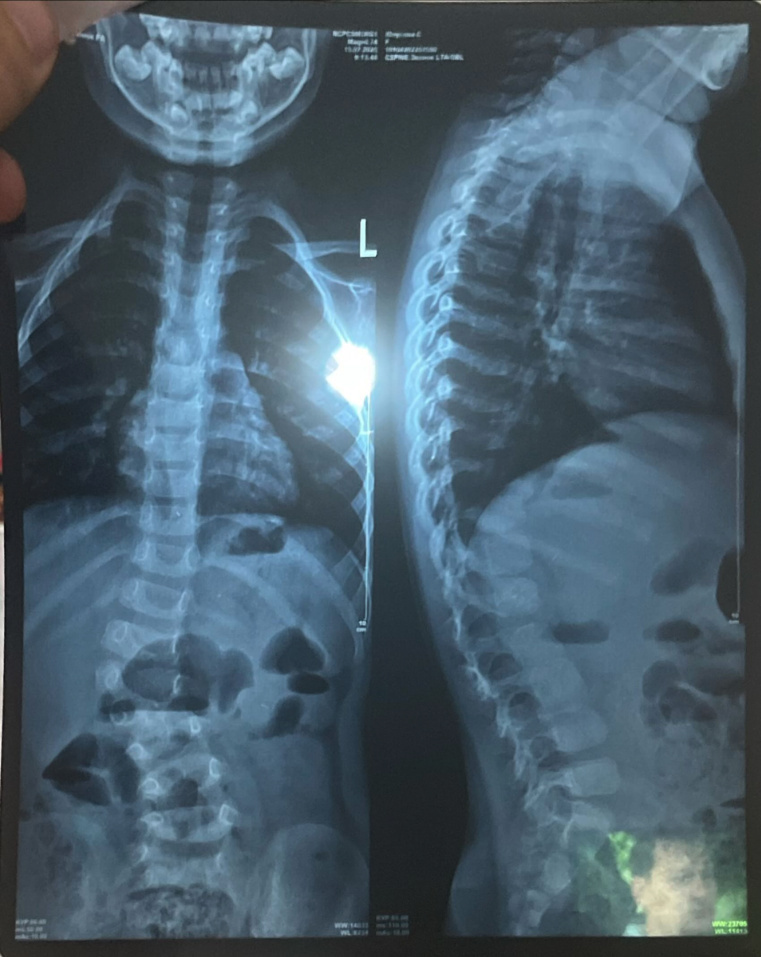

У нее сколиоз сложной формы. Из-за заболевания девочке трудно быстро ходить и бегать, поэтому большую часть времени она сидит или лежит.

"Поняв, что ничего не помогает, мы обратились к профессорам из Турции. Они считают, что единственное решение - это операция, и чем скорее ее проведем, тем лучше для дальнейшего роста и развития Сумаи. А недавно мы узнали еще, что у нее есть лишняя кость на позвонке (отросток видно на рентгеновском снимке). Это тоже следствие сколиоза", - говорит мама.

Искривление позвоночника уже привело к асимметрии тела, у малышки одно плечо стало ниже другого, а одна нога короче другой.